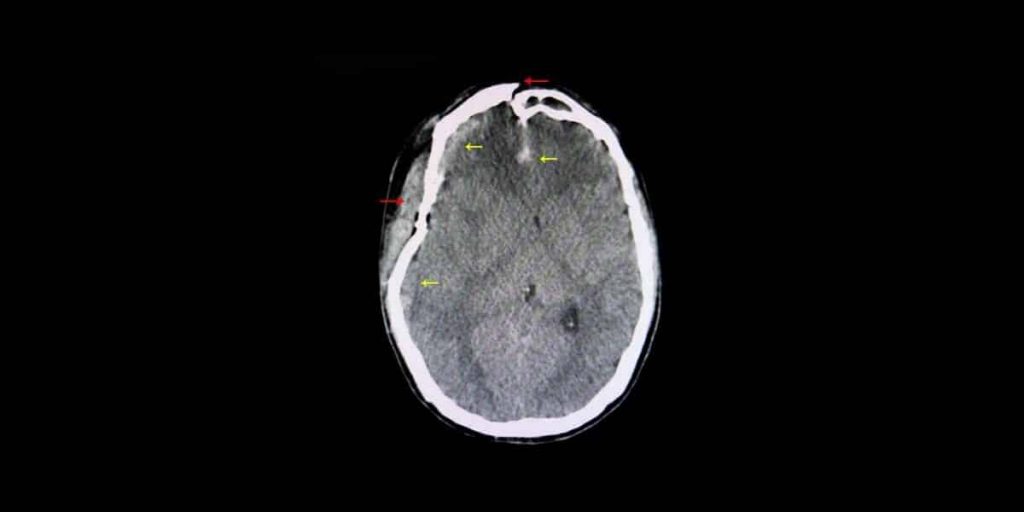

Traumatic brain injury after a car accident Thunda Funda

Brain Bleed From Car Accident What You Need To Know What Happens To The Brain After A Car Accident Brain damage can occur following a traumatic injury, such as a fall or car accident, or a nontraumatic, acquired injury, such as a stroke. Traumatic brain injury (tbi) refers to damage to the brain caused by an external physical force such as a car accident, a gunshot wound to the. For some brain injuries, like. If you have been in. What Happens To The Brain After A Car Accident.